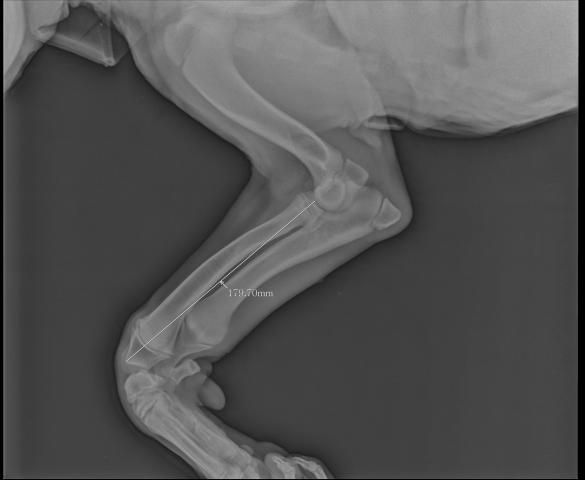

Размет передних лап

Причин размета лап может быть несколько. Как вы нагружаете свою собаку? Причина может быть в повешенных или пониженных нагрузках. Вы держите собаку дома или на улице? Если собака домашняя, то причиной часто служит скользкое напольное покрытие(ламинат), собаке необходимо ходить по песку, щебню. Так же необходим анализ крови на витамины и кальций-фосфорное отношение. Какой рацион кормления у вашего щенка? Хватает ли ему минеральных веществ и витаминов для развития костной ткани суставов. Необходимо включит в рацион мясо-костную муку, рубец и субпродукты, рыбную муку, творог.